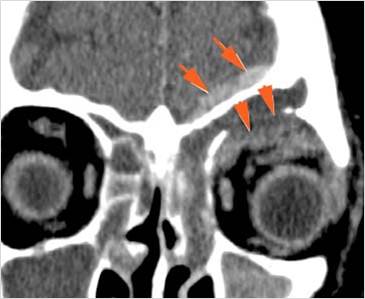

Orbits

The extraconal orbital fat is abnormal. [Yes/No]

There is a subperiosteal abscess or edema along the medial wall, roof or floor of the orbit. [Yes/No]

The extraocular muscles are swollen or otherwise abnormal. [Yes/No]

There is bone erosion along the walls of the orbit. [Yes/No]

The intraconal orbital fat is infiltrated. [Yes/No]

The orbital apex and the superior and inferior orbital fissures are infiltrated. [Yes/No]

The superior and/or inferior ophthalmic veins are dilated or thrombosed. [Yes/No]